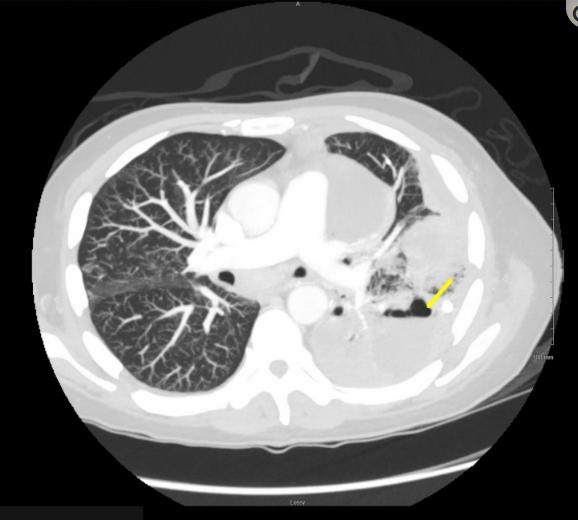

两天后进行胸管放置。患者接受了两剂组织纤溶酶原激活物(tPA)和丹纳酸酶阿尔法,一天后,当胸腔液分析显示血细胞比容为23%时,引起对血胸的关注,因此停药。使用左旋唑啉7天后仍有白细胞增多,因此改用头孢唑林。入院后8天的复查发现左腔病变恶化,未被胸管完全排空。也有进行性双侧肺实变,涉及坏死性肺炎。感染性疾病使患者转用静脉注射头孢吡肟和鞭毛灵的两周疗程。咨询了心胸外科和介入放射学,并决定在入院后13天使用tPA进行第二次左心尖胸导管放置。两个胸管在四天后被移除;两者的排出量都很低。胸部x光显示有稳定的积液,患者随后在三天后出院(图​(图3)。

图3、入院时胸部x光显示稳定的左侧胸腔积液相对没有变化